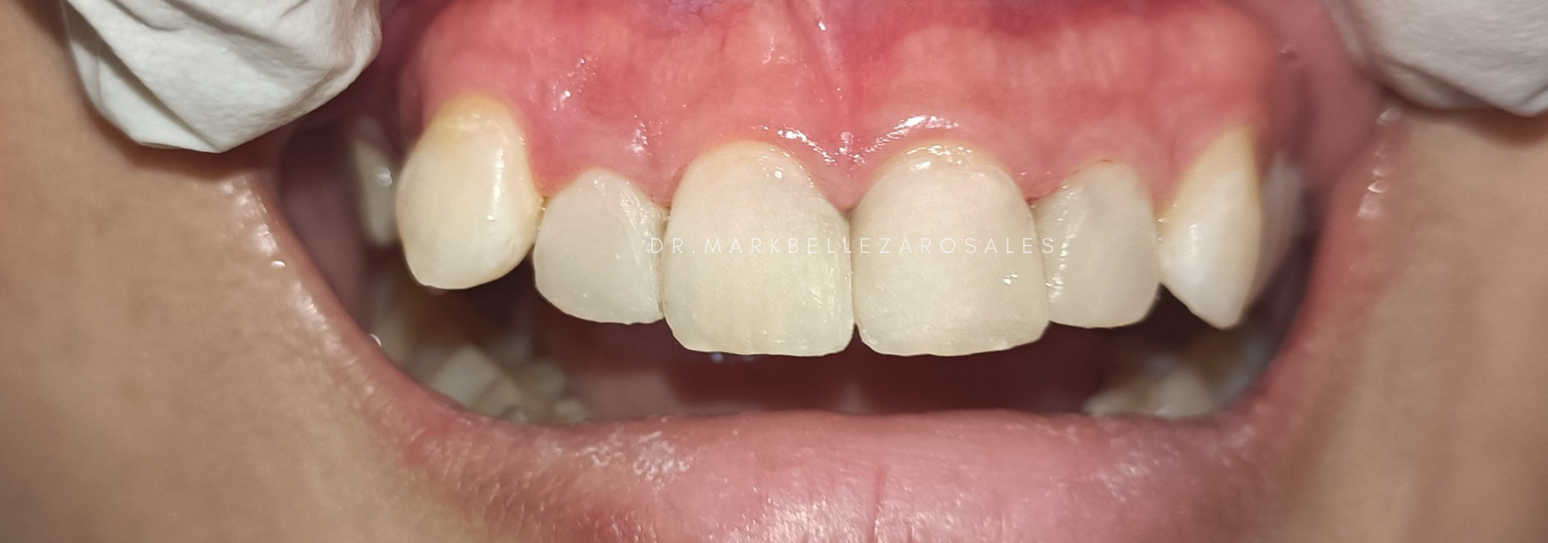

Porcelain bridges are dental restorations used to replace one or more missing teeth by filling the gap with tooth-colored artificial teeth supported by nearby natural teeth. They are designed to look natural, restore proper chewing and speech, and blend smoothly with your existing smile.

A porcelain fused metal bridge is a fixed dental restoration used to replace missing teeth by combining a strong metal framework with a porcelain exterior. It offers durability and support while maintaining a natural tooth-like appearance for effective chewing and a balanced smile.